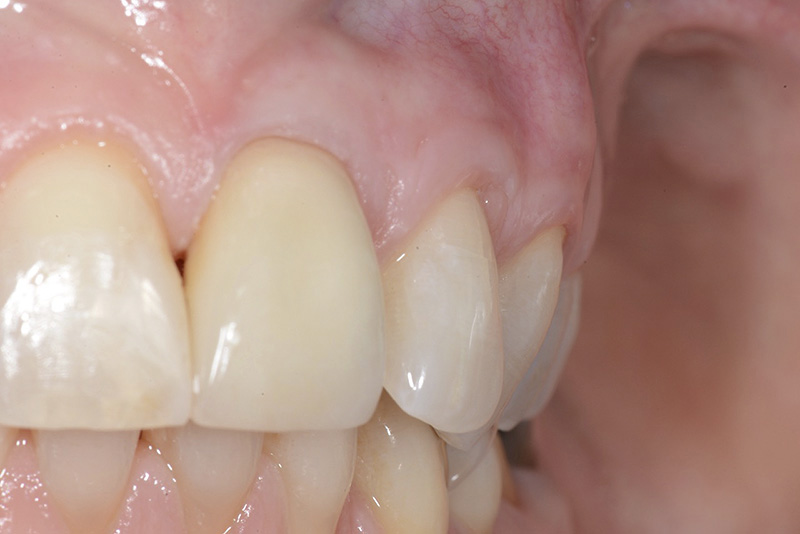

Vengono utilizzati 2 tipi di provvisori: il primo, cementato ai denti vicini, viene utilizzato dal momento dell’estrazione del dente fino ad impianto osteointegrato (circa 6 mesi); il secondo, avvitato direttamente all’impianto, ha una funzione di prova estetica ma soprattutto di guida per la maturazione dei tessuti gengivali peri-implantari portandoli verso la maturazione completa prima di posizionare la corona finale in disilicato di litio.